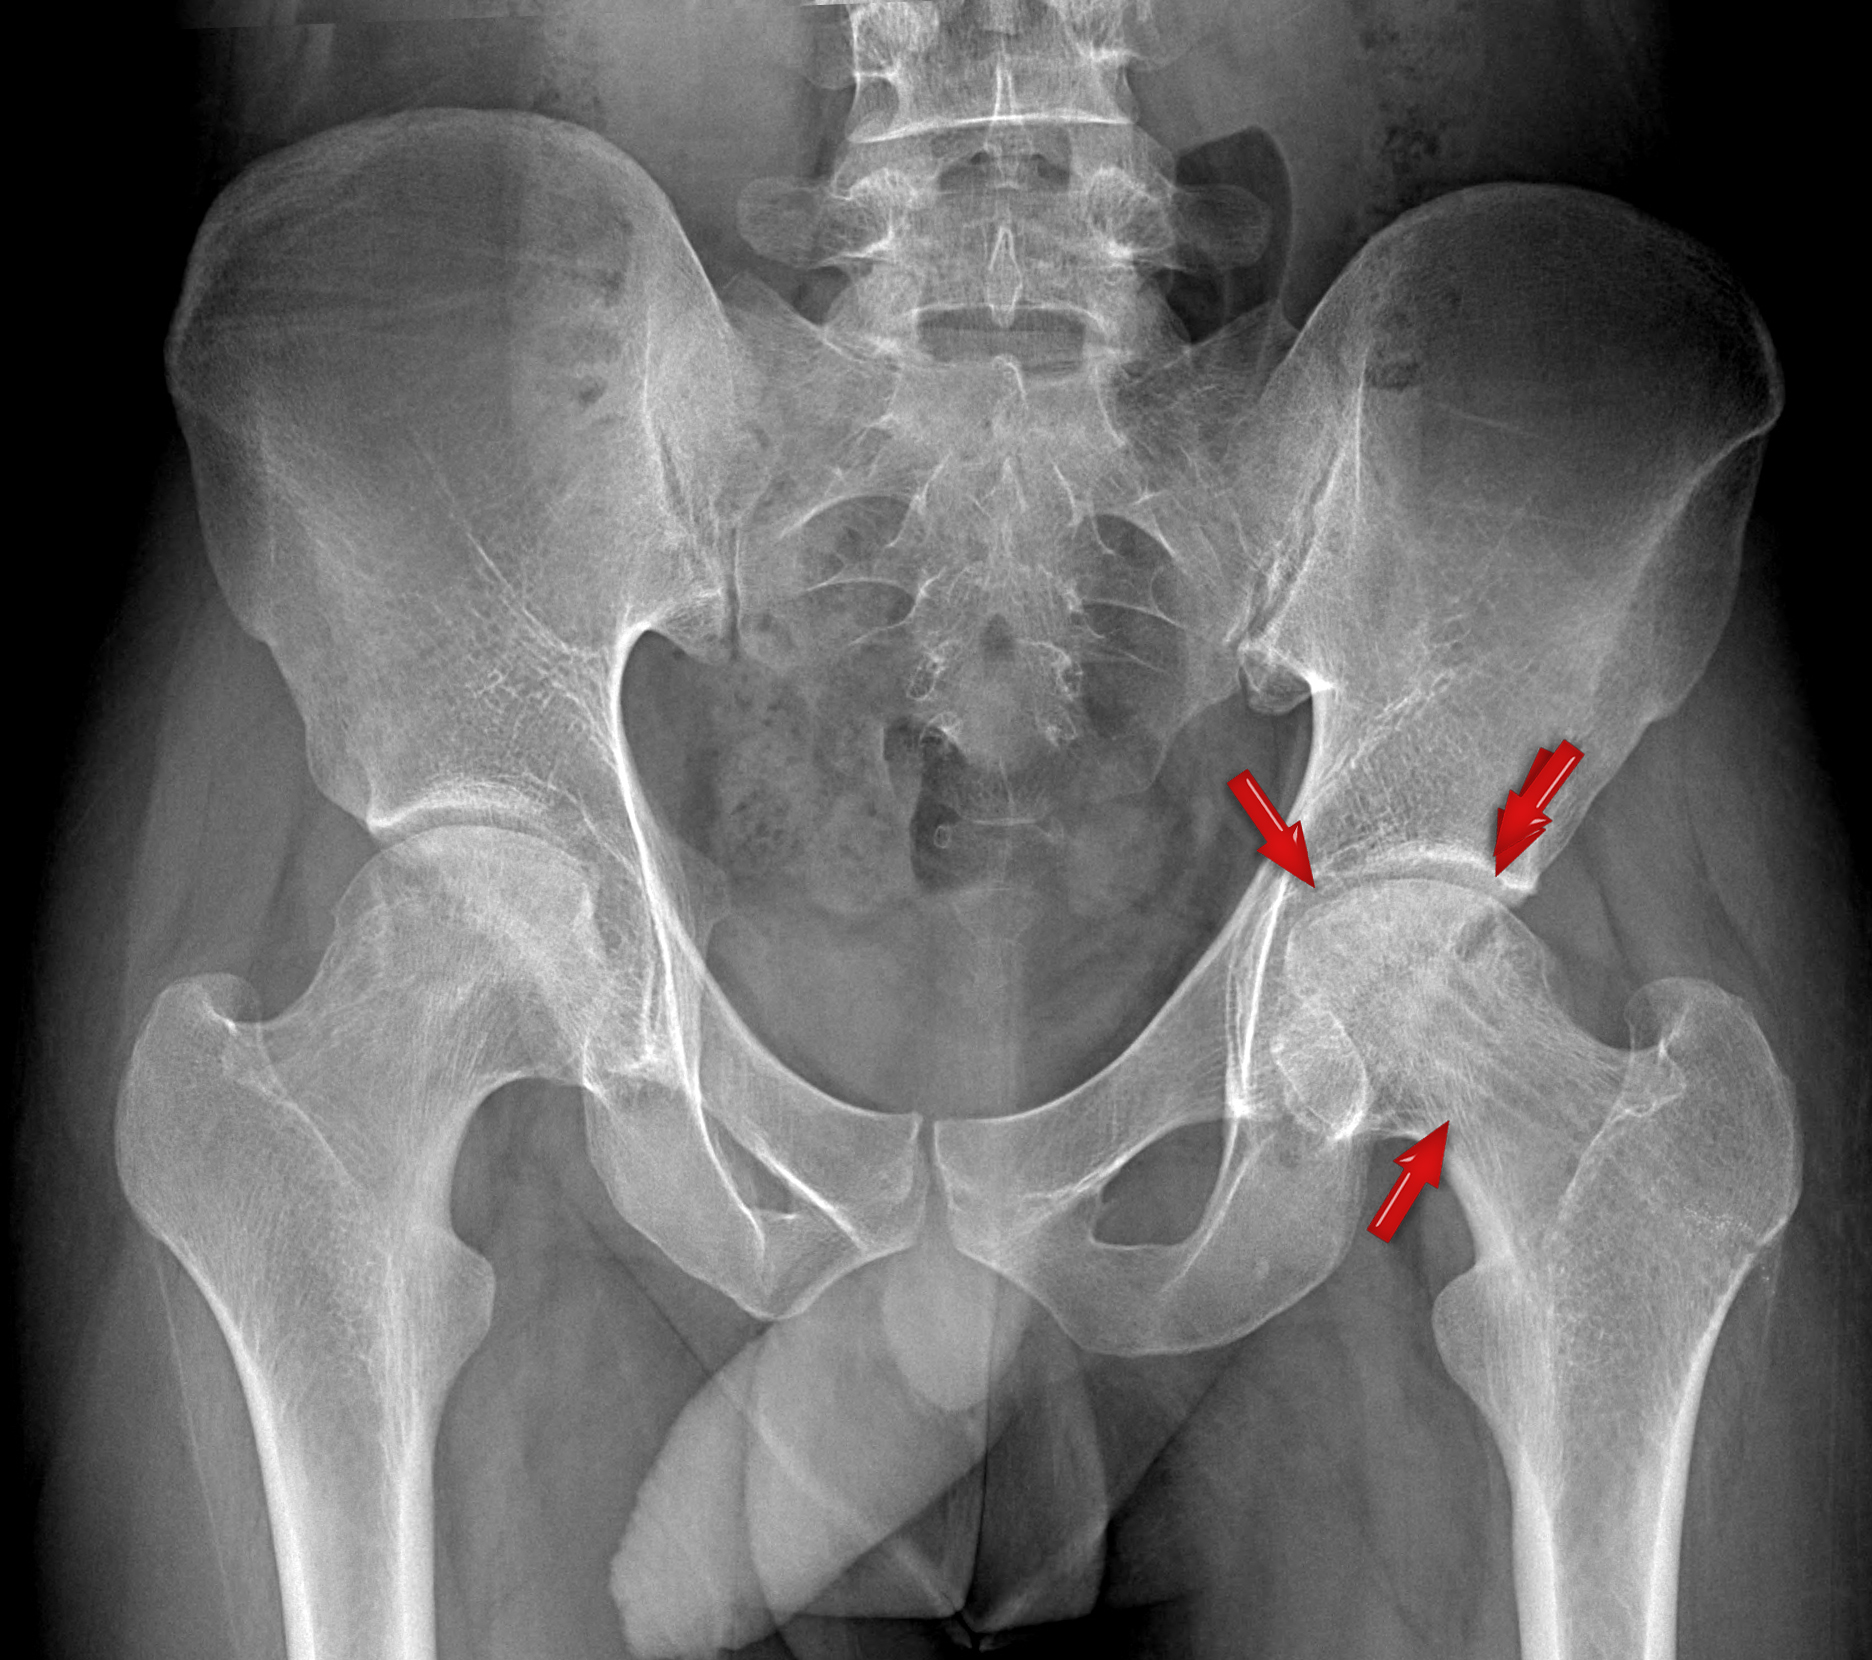

Avascular necrosis of the Hip Joint

avn postop